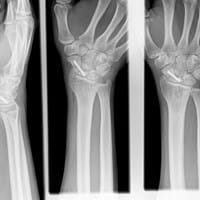

Quería saber, cuál es tu opinión de esta radiografía de una fractura de escafoides que he sufrido?

Cual es vuestra opinión de esta radiografía de una fractura de escafoides que he sufrido?

En Enero me han operado de una fractura de escafoides del polo proximal con un tornillo y un injerto de hueso. El caso es que mi traumatólogo insiste en esperar a ver como evoluciona el hueso hasta Agosto y el médico privado, me ha dicho que me...